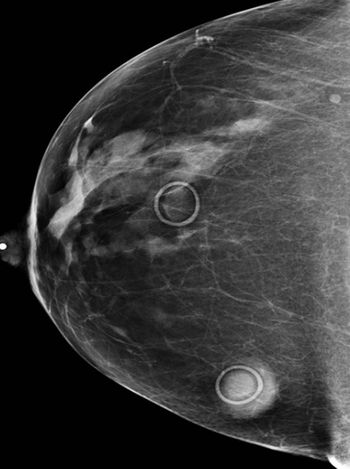

Adding one-view tomosynthesis to digital mammography improves diagnostic accuracy and reduces recall rates, but adding two-view tomosynthesis provides even better results.

Digital mammography with a photon-counting system had higher cancer detection rates than traditional systems.